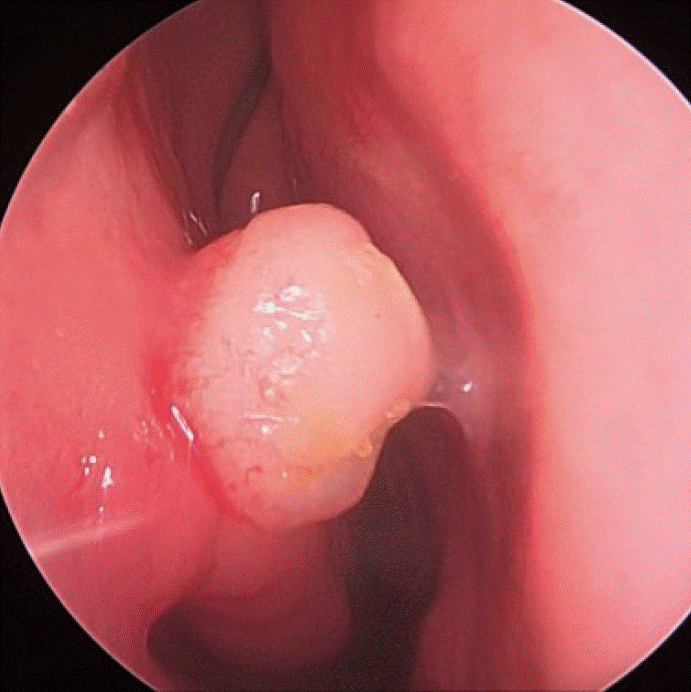

Upon physical examination, nasal endoscopy revealed a smooth, round, and vascular-appearing mass with a relatively regular margin (Fig. 1).

Nasal endoscopic finding of angioleiomyoma showing round-shaped mass with a relatively regular margin at the head of the right inferior turbinate in patient 4.